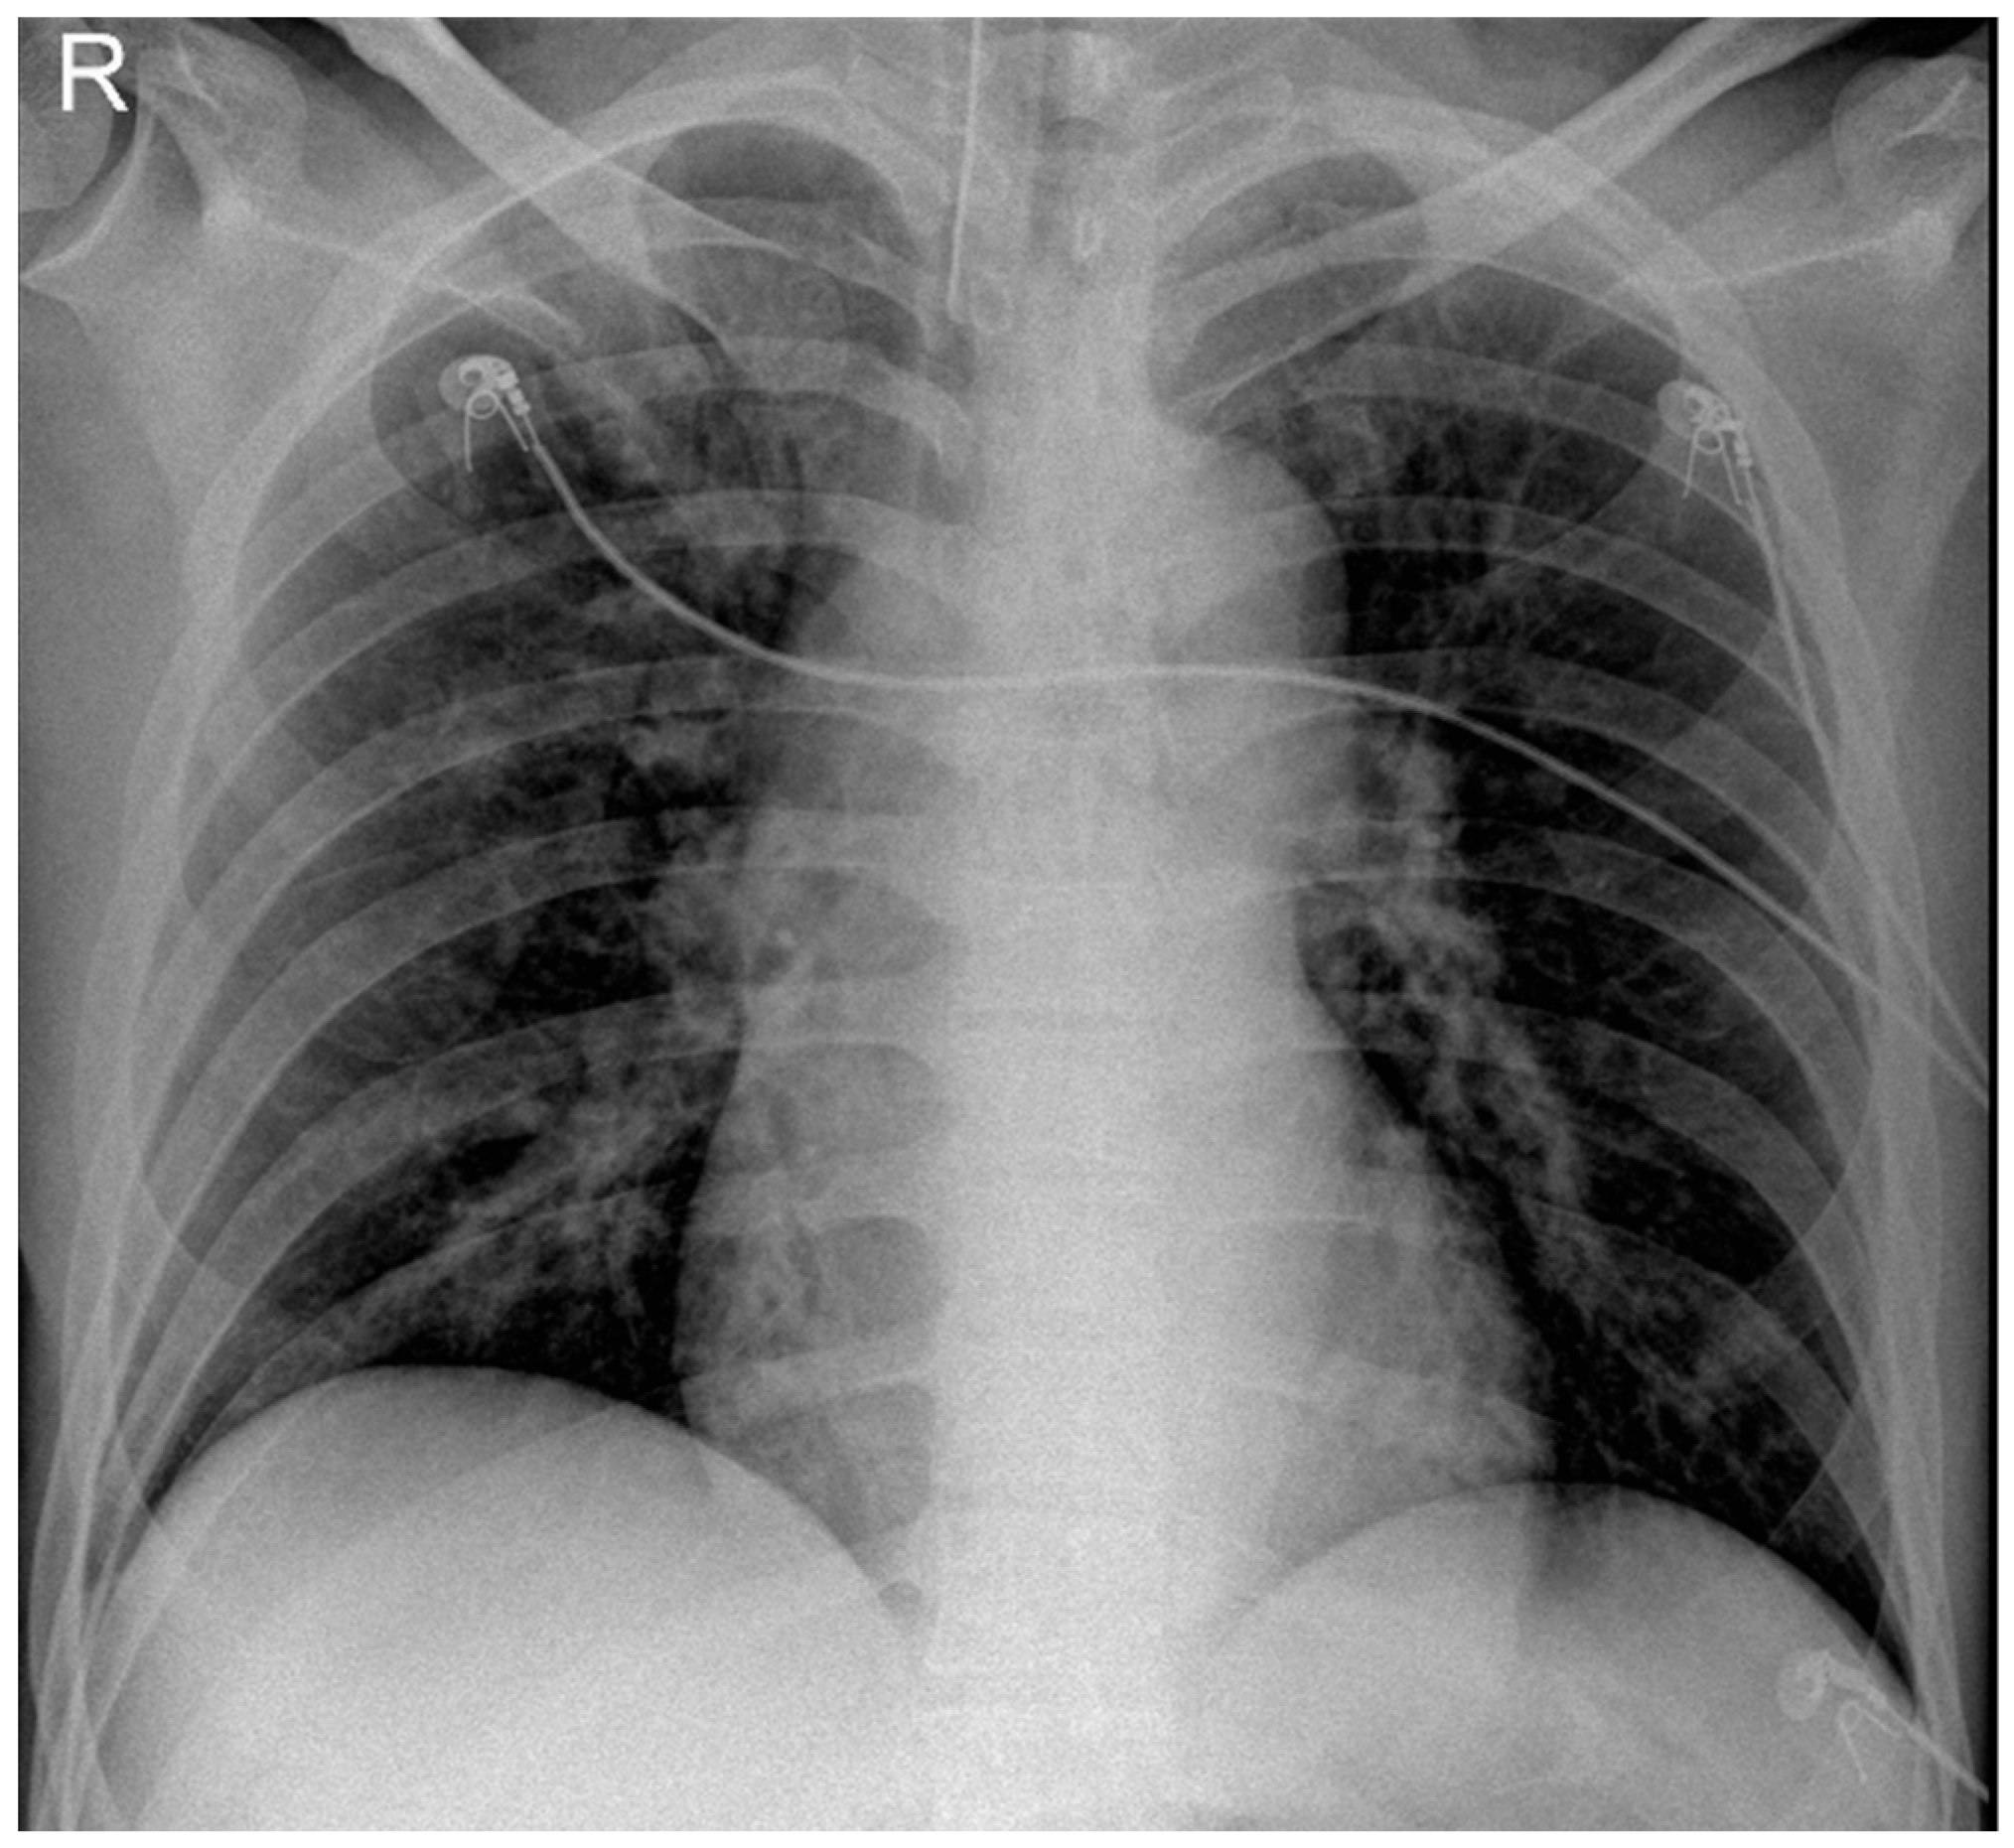

He returned to ED three days later with severe respiratory distress and was immediately transferred to the ICU and intubated due to hypoxia and increased work of breathing. Following intubation, he was hemodynamically stable. Physical examination revealed significantly decreased breath sounds bilaterally. Ventilator waveforms indicated high airway pressure and increased resistance. An urgent bronchoscopy was performed, revealing significant (>75%) narrowing in the main bronchus. Immediate debulking with biopsy forceps in the main bronchus was performed to assist ventilation. Bilateral main bronchi exhibited obstructive tracheobronchitis with prominent mucous plugs (Figure 1) and pseudomembrane (Figure 2). A bedside chest X-ray following intubation showed mild ground-glass opacification in the right lung (Figure 3). The CT scan performed the day after intubation and ICU admission revealed new bilateral patchy opacities and small nodular lesions in the lung parenchyma (Figure S2).

Figure 3. Chest X-ray following intubation showed mild ground-glass opacification in the right (R) lung.